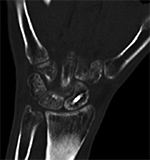

Fracture healing and joint fusion may be assessed readily with radiographs, but the presence of callus formation alone does not predict progression to complete healing, and the presence of osseous bridging is considered a more reliable indicator of union (Figure 9) (Ohashi, 2009). CT has been found to be more accurate for the determination of osseous bridging, as radiographs may either underestimate or overestimate the extent of bone fusion (Krestan, 2006; Grigoryan, 2003). The presence of exuberant callus formation may obscure the evaluation for osseous bridging on radiographs, and multiplanar CT allows direct visualization of the fracture site. In addition, fine central osseous bridging at the site of small fractures and bone grafts, such as in treated, non-united scaphoid fractures, is better assessed with thin slice CT images (Figure 10). Finally, some articulations are difficult to assess due to overlapping anatomy, such as the posterior subtalar and Lisfranc joints, and CT offers superior delineation of the joint spaces following arthrodesis.

Scaphoid Fracture Evaluation. (A) Sagittal multiplanar reformation shows central portion of compression screw in the scaphoid with incomplete union at periphery of fracture site (arrowheads). Note absence of streak artifact due to small size of screw. (B) Coronal multiplanar reformation shows fracture union at the central portion of the scaphoid waist, indicating partial union.